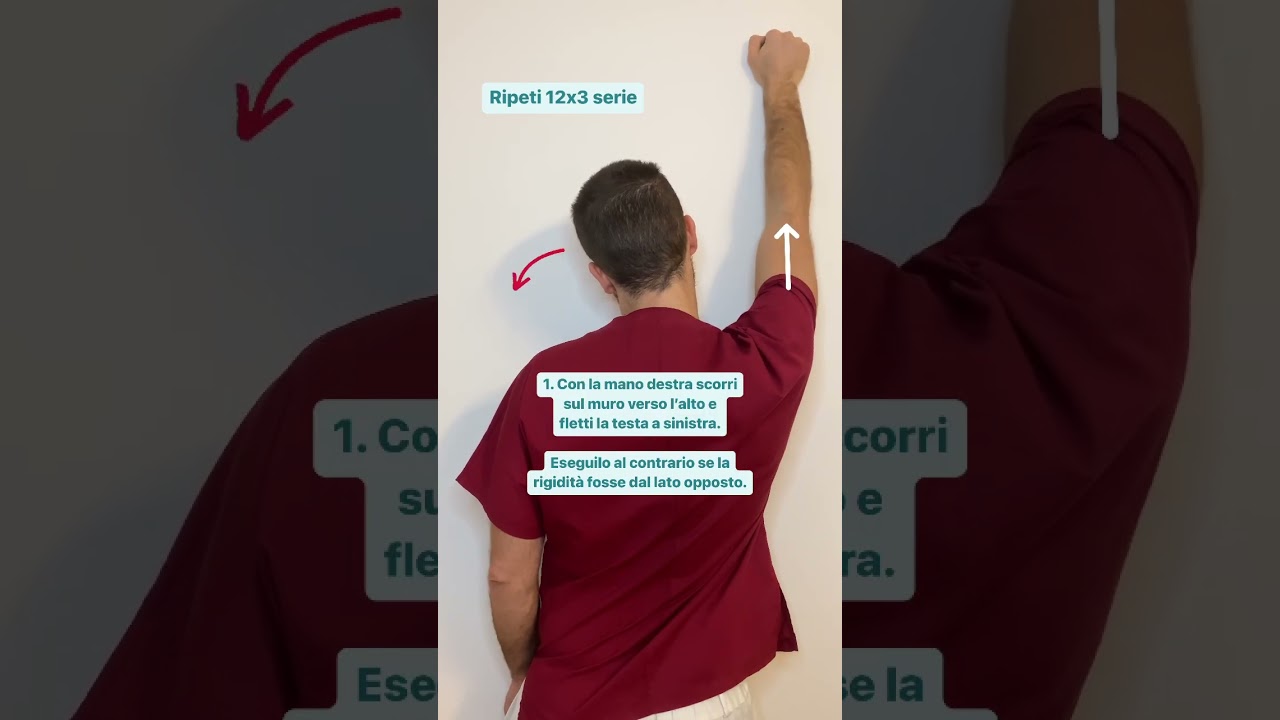

Video Hai il collo bloccato🚫 #cervicale #postura #osteopatia virale

I muscoli del collo sono particolarmente delicati, in quanto subiscono l'influenza di numerosi fattori, tra cui spicca sicuramente lo stress emotivo, che può portare ad avere i muscoli del collo contratti e il collo bloccato.

Lo stato di eccessiva contrattura muscolare a livello cervicale è estremamente comune, diciamo pure che è la "base" del disturbo cervicale.

Una volta che questo stato si è cronicizzato, la cosa migliore che possiamo fare è quella di stimolare positivamente la muscolatura tramite movimenti specifici e tecniche mirate: scopri un semplice ma efficace esempio.